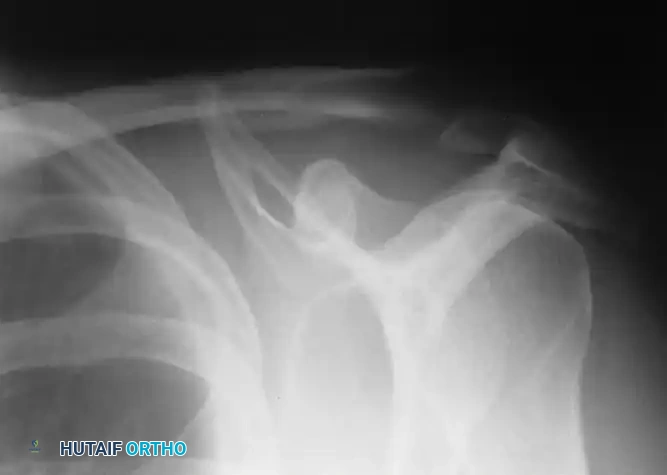

Painful syndromes, altered kinematics, and signs of instability or internal derangement are ubiquitous in the shoulder joint. The precise etiology of such dysfunctions can frequently elude standard clinical detection. While the underlying cause can often be established through a meticulous history, provocative physical examination, and appropriate radiographic evaluation of the shoulder girdle, cervical spine, and thoracic cavity, diagnostic ambiguity remains a clinical reality.

Special diagnostic modalities—including stress radiographs, computed tomography (CT), magnetic resonance imaging (MRI) with and without intra-articular gadolinium contrast, electromyography (EMG), and nerve conduction velocities (NCV)—are invaluable. However, when these non-invasive or minimally invasive studies remain inconclusive, diagnostic arthroscopy provides the ultimate direct, dynamic evaluation of the glenohumeral joint and subacromial space. Seminal research by Andrews, Carson, and Ortega demonstrated that arthroscopic examination of chronic, undiagnosed painful shoulders revealed one or more significant intra-articular abnormalities in 88% of patients.